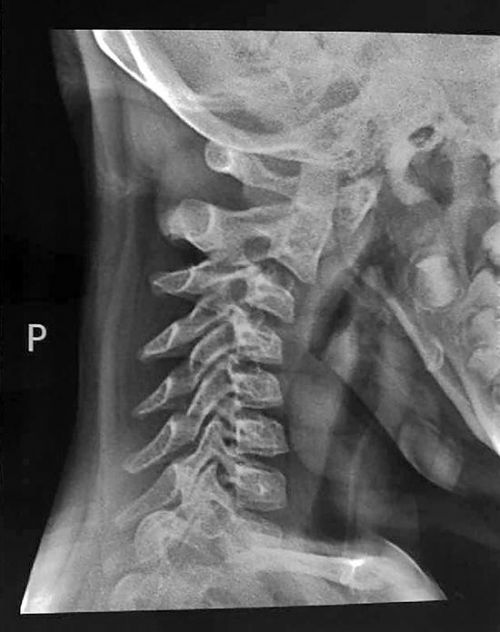

Qua quá trình chụp X – quang, bác sĩ phát hiện 3 đốt xương cổ đầu tiên của Doanh Doanh đều bị chệch khỏi vị trí.

Hình chụp X - quang xương cổ của Doanh Doanh. (Ảnh: nguồn internet)